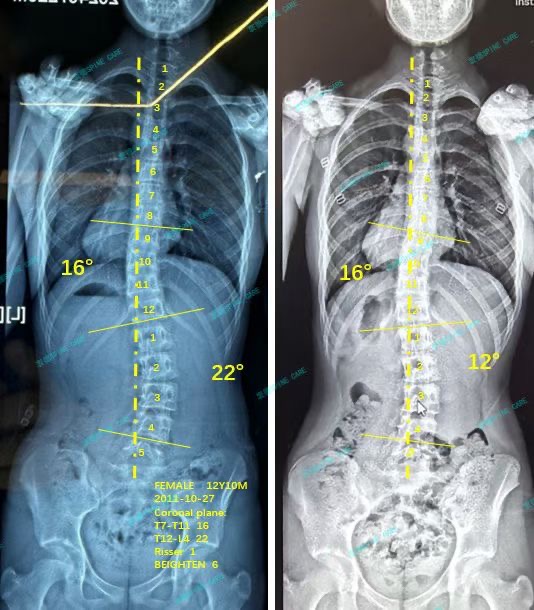

我是曦曦,22度腰弯降至12度,我坚持下来了!

案例主人:曦曦 发现侧弯年龄:12岁 侧弯情况:Cobb角度22度

最近拍片发现我的腰弯从22度降至12度,体态也比以前对称了不少,我和妈妈都十分高兴,感谢杨博士,也感谢衷德团队,我会继续加油的!

Recently, I found that my waist bend has dropped from 22 degrees to 12 degrees, and my posture has become much more symmetrical than before. My mother and I are very happy. Thanks to Dr. Yang and Zhongde's team, I will continue to work hard!